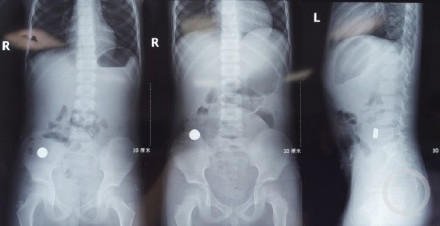

“腹腔镜进去后,发现第一枚磁铁是在升结肠的位置,第二枚磁铁在距离小肠的末端——距离回肠大概五六十厘米的地方,两枚磁铁紧紧地吸在一起,中间还夹住了一块小肠。”主刀医生普外新生儿外科袁亮主治医师回忆,取下磁铁后,又发现天天有四处肠穿孔,只有将坏死的肠管进行切除后缝合,“磁铁的吸力很强,成人用手将磁铁掰开也需要花不小的力气。”目前天天已经顺利出院。